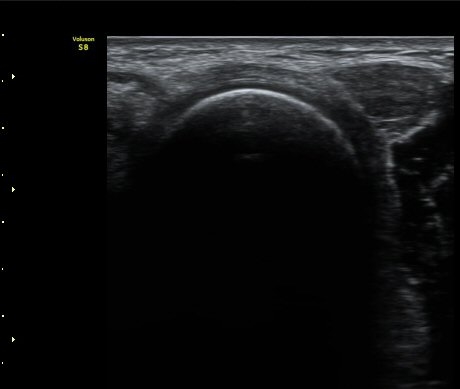

ÆÈ²ÞÄ¡ ¿ÜÃø¿¡¼­ ½ÃÇàÇÑ ¿ä°ñµÎ Á¾´Ü¸é°Ë»ç¿¡¼­ ¿ä°ñµÎ¿Í ¿ä°ñ °æ°èºÎ°¡ ¿¹°¢À¸·Î ÀÌÇàµÇ°í

°æ°èºÎ¿¡ ¼Ò·®ÀÇ ¼ö¾×Àú·ù°¡ °üÂûµÊ(±×¸² 2)